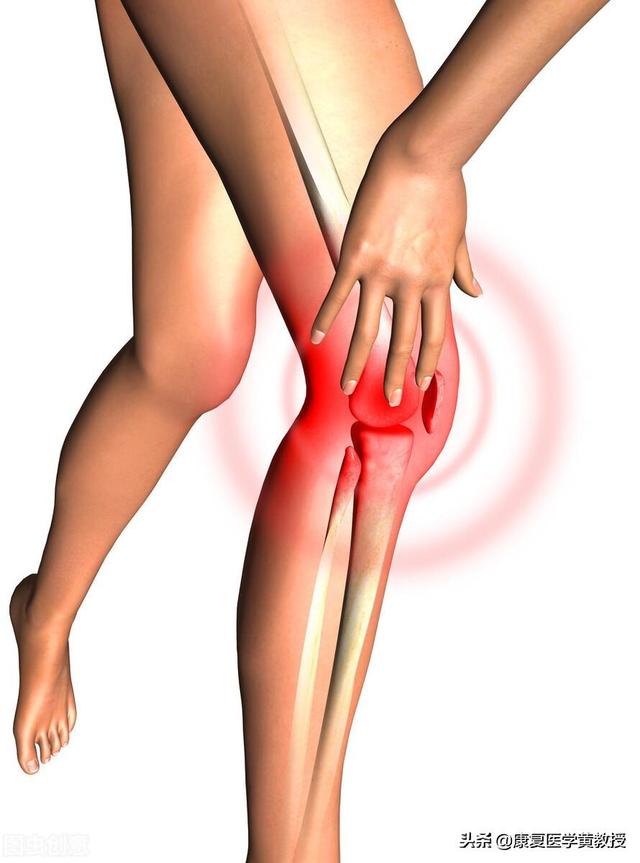

Les patients souffrant d'arthrose à un stade précoce présentent souventTension derrière le genou.auraitFaiblesse des articulationssurtout s'il y auralit. battre ses jambes faiblesLa manifestation de la maladie, chez certains patients qui s'accroupissent, se traduit par des craquements évidents des articulations et s'accompagne de douleurs. Au fur et à mesure que la maladie s'aggrave, les symptômes du patient deviennent plus sévères, et certains patients présentent peu à peu des symptômes d'arthrose.Douleur dans les articulations lors de la montée et de la descente des escaliers et lors de la marche sur terrain plat.Dans les cas les plus graves, les patients peuvent présenter des douleurs articulaires même au repos, avec desTroubles de la mobilité articulaire et déformations des articulations。

Avec l'âge, les tendons et les ligaments de l'articulation du genou commencent à subir des changements dégénératifs et la production de liquide synovial dans la cavité articulaire diminue ;

Les surfaces osseuses des articulations sont enÉtat de frottement à long termeLa dégénérescence du cartilage articulaire se produit progressivement et entraîne divers problèmes.

En raison de l'inflammation, des adhérences sont particulièrement susceptibles de se produire, et les personnes âgées ressentent souvent une raideur dans les articulations du genou, avec des bruits de claquement ou de frottement lorsqu'elles se déplacent